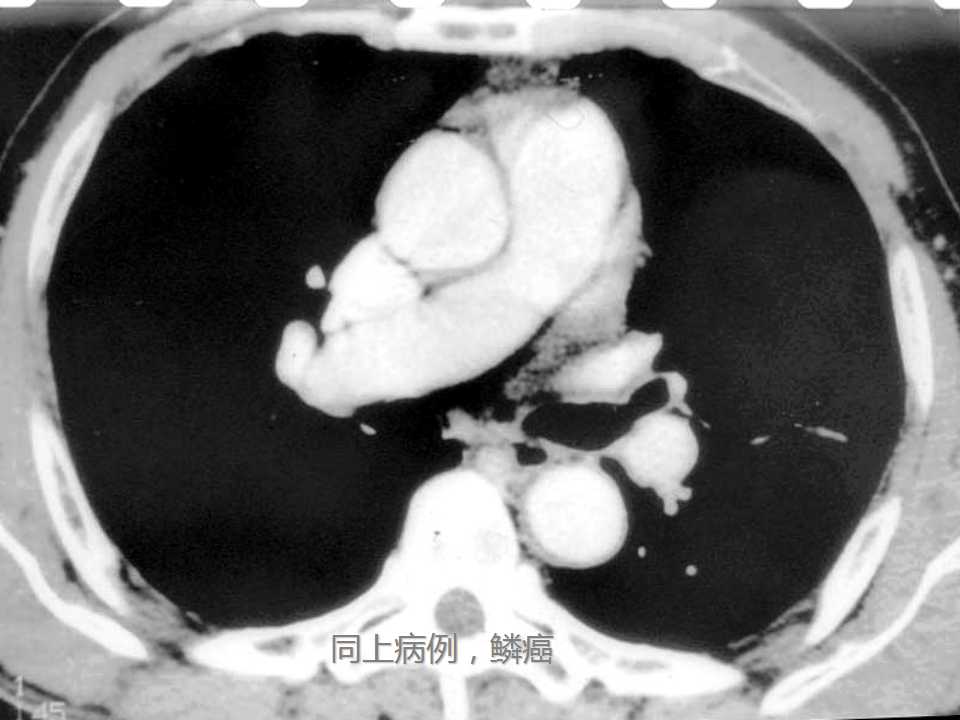

肺癌影像学表现